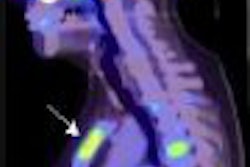

The study, presented at this week's annual meeting of the SNM in Washington, DC, considered 24 consecutive PET scans, which displayed 33 malignant lung tumors in 24 patients. Tumor size, which ranged from 5 mm to 28 mm, with a mean of 15 mm, was determined through the dual-slice CT portion of the PET/CT scan, with biopsies used to prove malignancies.

The analysis started with a set of 3D volumetric PET images. Each image was interpolated to form an isotropic image with a voxel size of 2.5 mm for the CAD algorithm to be effective.

Researchers followed with the application of a selective tumor enhancement filter. Applebaum described the filter as "a mathematical model" to favor tumor characteristics to aid in the detection of initial tumor candidates and suppression of normal anatomic structures.

For each tumor candidate on the original and enhanced image, researchers also determined 12 features, including average standardized uptake value (SUV), standard deviation of the SUV, diameter, spherical characteristics of the tumor, irregularity, and standard deviation for tumor enhancement filter.

"With this initial filter application, our sensitivity was very good -- 94%-- as 31 of 33 tumors were detected," Applebaum said. "As would be expected at this stage, there was a very high false-positive rate -- 21.5% false positives per scan -- which would be an unacceptably high for a screening CAD tool."